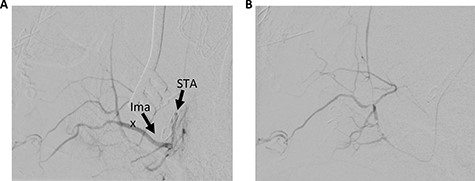

The patient underwent a left preauricular incision to isolate the STA from surrounding parotid parenchyma by the Head & Neck Surgery team. Under microscopic guidance, the STA was cannulated with an 18-gauge angiocatheter (Fig. 2) by the Neurosurgery team, which was secured in place with 2-0 silk suture. A rotating hemostatic valve (Abbott Laboratories, Chicago, IL) was attached to the angiocatheter and a retrograde angiogram was performed, confirming STA access (Fig. 3A). An Echelon 10 microcatheter (Medtronic, Minneapolis, MN) and a Synchro 14 microwire (Stryker, Kalamazoo, MI) were then used to select the proximal left IMA for digital biplane angiography. Hand-injected control angiography confirmed appropriate microcatheter positioning, demonstrating opacification of the left IMA and branches, with nonspecific contrast blush including the left sphenopalatine arteries. Thereafter, liquid embolization using Onyx® Liquid Embolic System (Medtronic, Minneapolis, MN) was performed to occlude the IMA. A final angiogram demonstrated satisfactory occlusion of the left IMA without evidence of extravasation, aneurysm or pseudoaneurysm (Fig. 3B). The STA was decannulated and ligated, and the preauricular incision was closed primarily.

Cannulation of the STA through preauricular incision (A). Multilayered closure with superficial glue following decannulation (B).